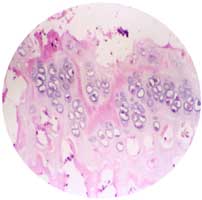

大块的异体骨具有一定支撑力,可用于节段骨缺损的修复。但大块异体骨的缺点是新骨长入慢,如果能够改善这个问题,对使用大块的异体骨修复大段骨缺损有重要意义。 理想的方法应该是(1)可靠适宜的固定。修复材料具有(或与其他固定物共同)使构建的骨产生有功能的达到设计要求的形态、几何形状、足够的生物力学强度;(2)补充充足成骨基质。材料具有成骨细胞容易贴附、增殖的界面,有利于营养成分的渗透的三维多孔结构;具有良好生物相容性;来源充足,易塑型。(3)提高骨折端的成骨活性。骨修复早期局部维持较高浓度的骨生长因子因子。 我们首次将神经肽以及BMP加强胞间通讯、促进成骨细胞增殖、使处于增殖周期的细胞比例增加的机理用于骨组织工程学的研究,用于解决骨组织工程学的研究成骨细胞增殖速度慢的难题,获得初步满意的效果。 成骨细胞可长入异体骨的骨孔中,呈单层贴壁生长,长入深度和成骨细胞数量均大于对照组。异体骨-成骨细胞复合物植入大鼠软组织,显示良好成骨活性,成骨量显著高于对照组。

成骨细胞—神经肽以及BMP异体骨复合物, 体内植入,可见成骨细胞长入骨孔